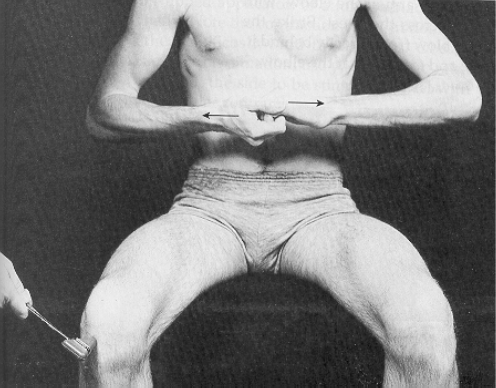

Kernig sign—inability to fully extend knees when patient is supine with hips flexed (90 degrees) caused by irritation of the meninges. Only present in approximately half of patients with bacterial meningitis

Brudzinski sign—flexion of legs and thighs that is brought on by passive flexion of neck for same reason as above; also present in only half of patients with bacterial meningitis

Jendrassik’s Maneuver Reinforcement technique Upper extremities

Lower extremities

- lock fingers and pull one against the other